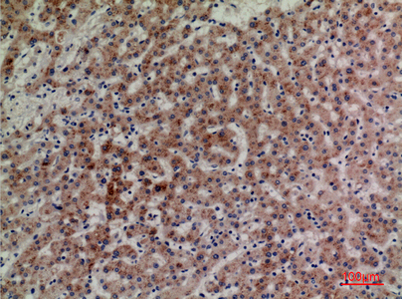

Product name: CD85g rabbit pAb

Dilutions: Western Blot: 1/500 - 1/2000. IHC-p: 1:100-300 ELISA: 1/20000. Not yet tested in other applications.

Immunogen: The antiserum was produced against synthesized peptide derived from the Internal region of human LILRA4. AA range:391-440